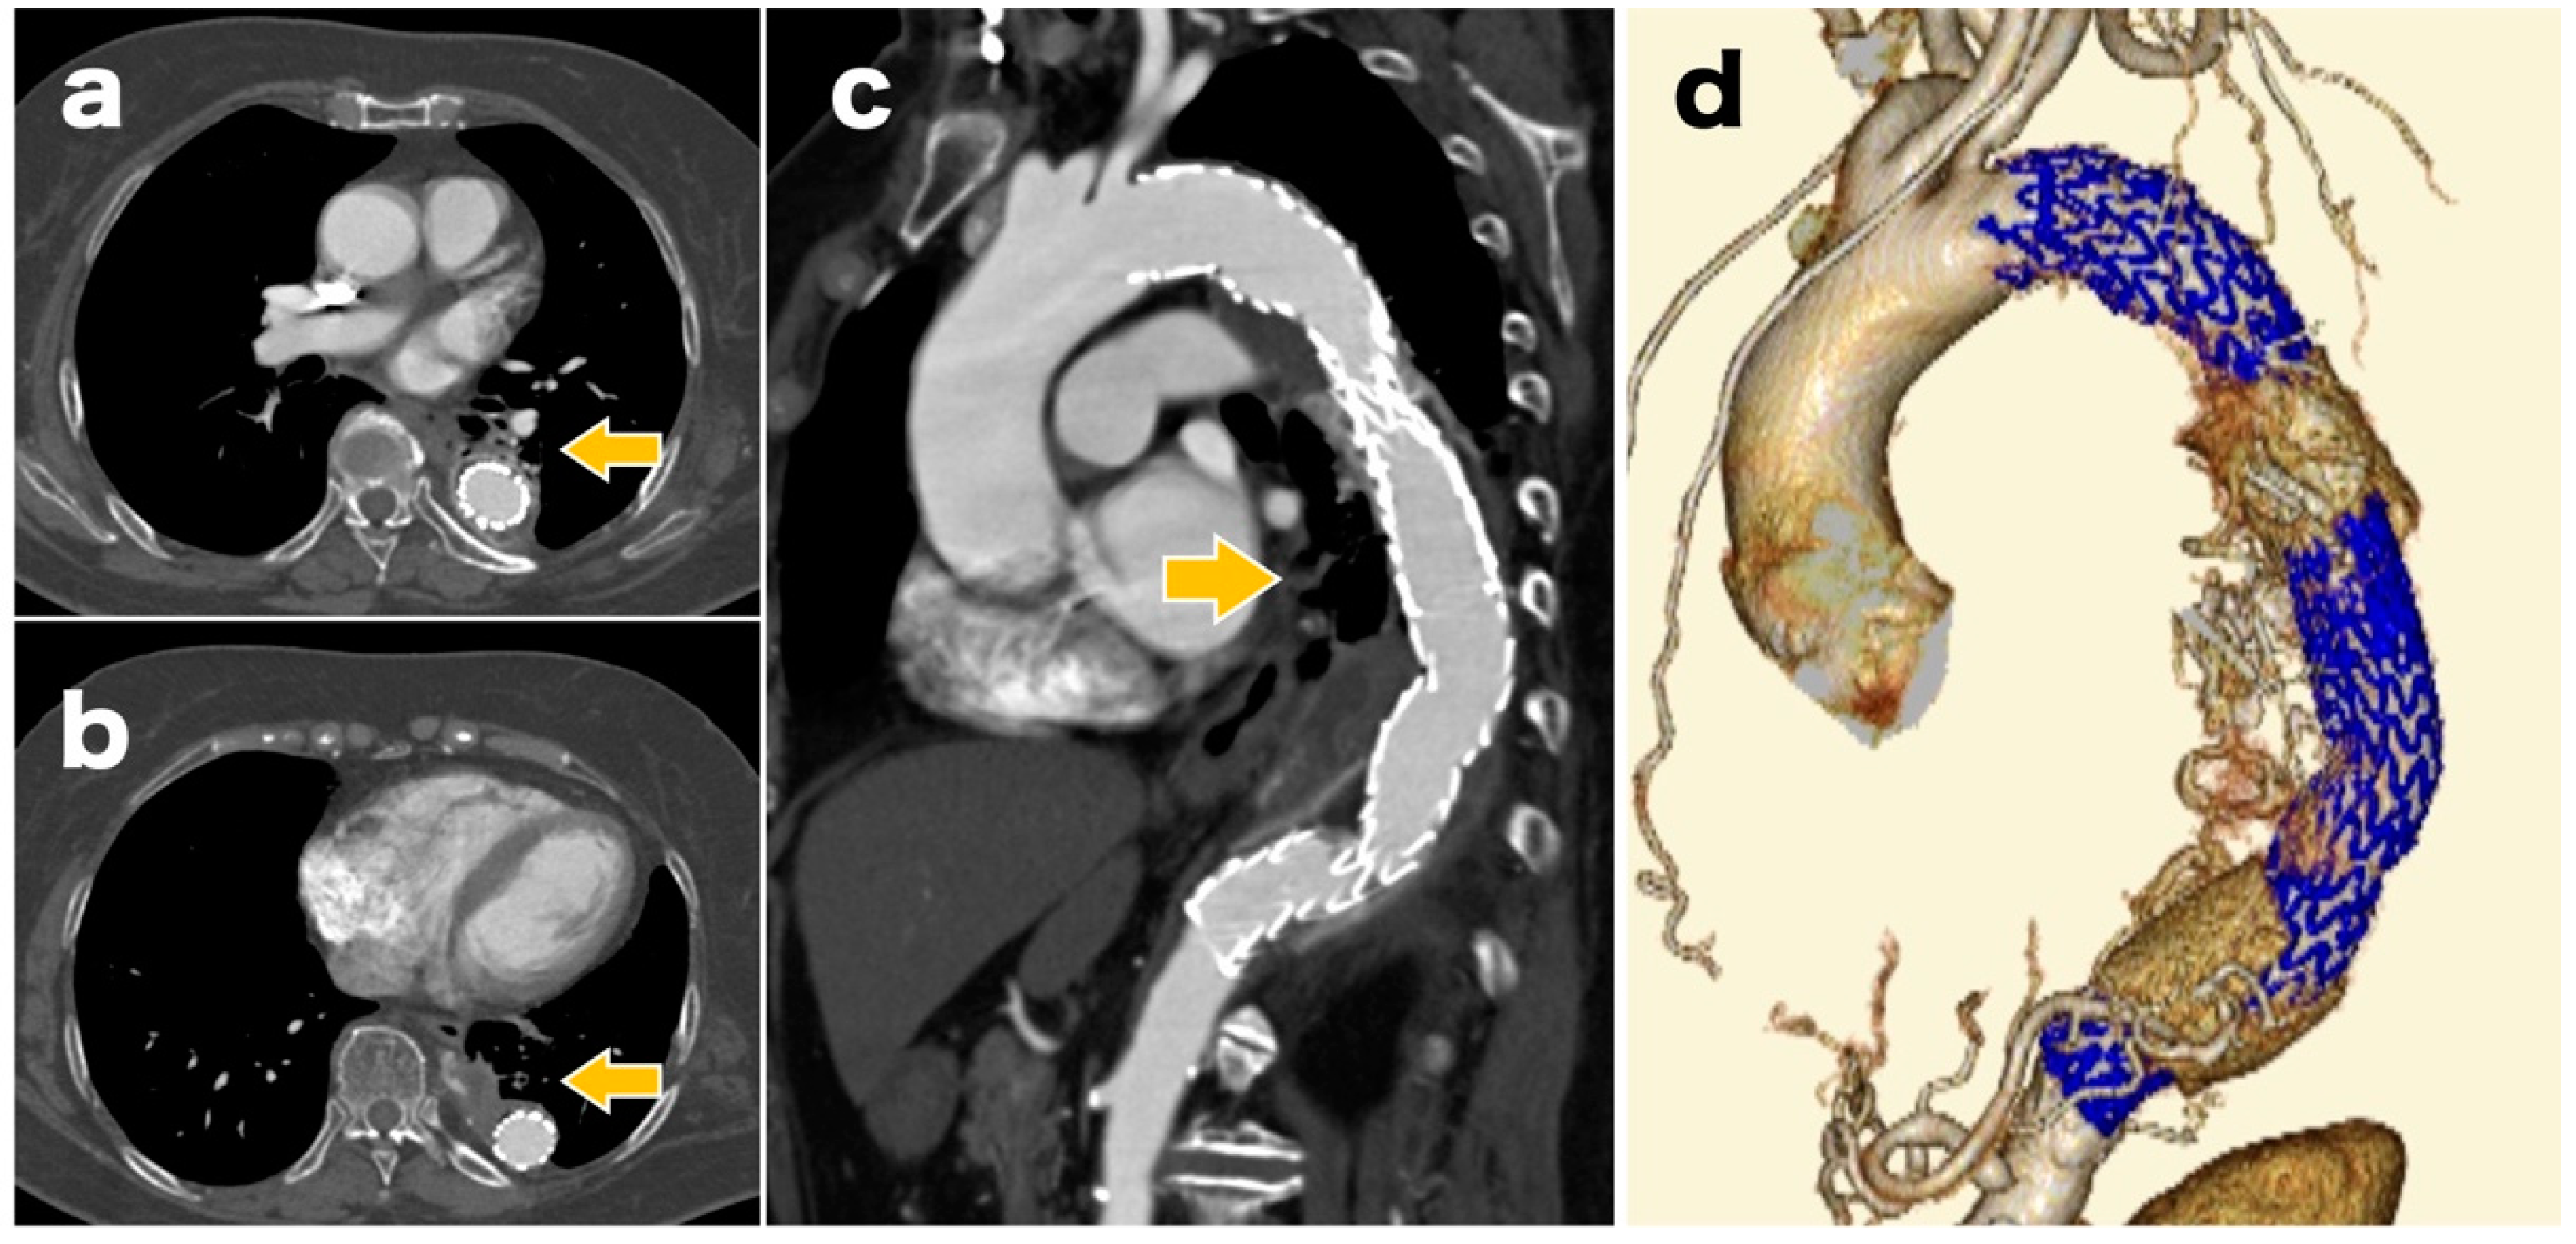

The surgery was performed under general anesthesia. First, a 26 × 26 × 200 mm stent graft (GORE® TAG® Conformable Thoracic Stent Graft with ACTIVE CONTROL System, W.L. Gore and Associates, Flagstaff, AZ, USA) was inserted at the distal site via the left common femoral artery. Subsequently, a 28 × 28 × 150 mm stent graft was inserted at the proximal site, and the region from Zone 3 was implanted at the level of the 12th thoracic vertebra (Figure 3). The final aortograph showed a slight type 1a endoleak, but ballooning was not performed because of the known dissection findings on the proximal side.

Figure 3. Postoperative contrast-enhanced computed tomographs showing no migration or fracture of the stent graft and no obvious endoleak.